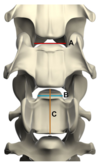

- How is the ratio measured?

- What value confers a 90% probability of spinal cord compression at that site?

- At what sites was there a significant difference in measurement between affected and clinically normal dogs?

- As the ratio increases, how does the probability of spinal cord compression change?

- Ratio = A/B (see image)

- What value confers a 90% probability of spinal cord compression at that site? Ratio = 0.4

- At what sites was there a significant difference in measurement between affected and clinically normal dogs? C5-6 and C6-7

- As the ratio increases, how does the probability of spinal cord compression change? For every 0.1 incremental increase in ratio, there is a 65% decrease in the odds of spinal cord compression being present at that site

Martin-Vaquero, P. & da Costa, R.C. (2014) EVALUATION OF TRADITIONAL AND NOVEL RADIOGRAPHIC VERTEBRAL RATIOS IN GREAT DANES WITH VERSUS WITHOUT CERVICAL SPONDYLOMYELOPATHY. Veterinary Radiology & Ultrasound 55, 488–495